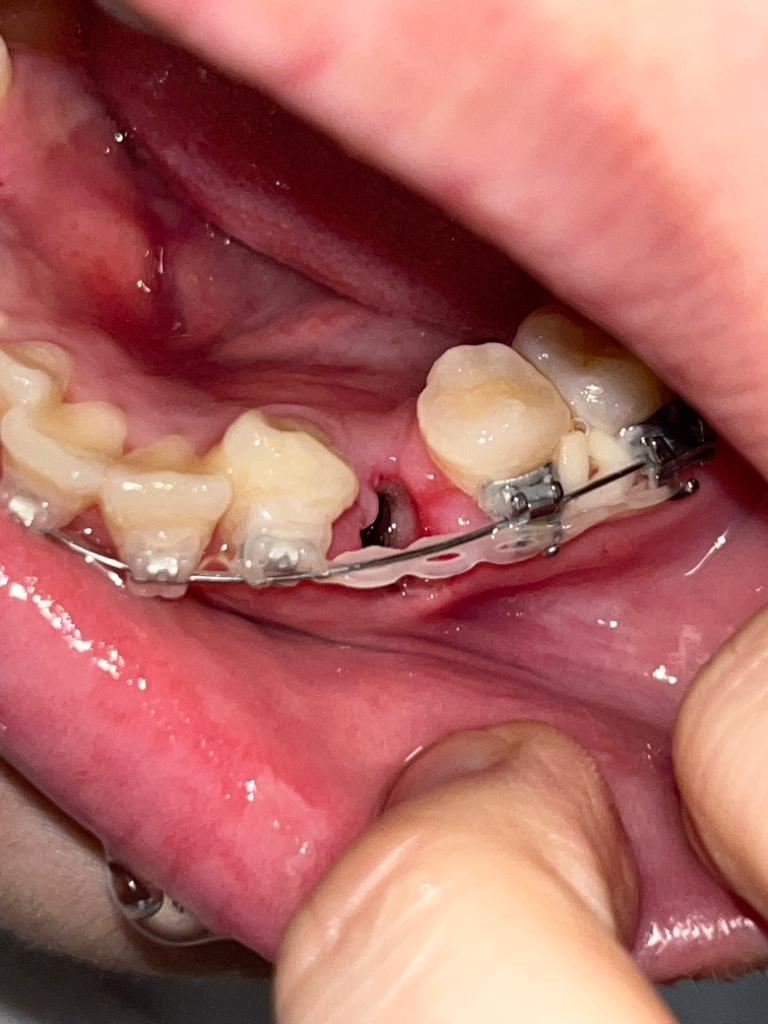

교정발치 3일차 드라이소켓인가요 ㅠㅠ

아플때마다 진통제 먹으면 괜찮아집니다 ㅜㅜㅠㅠ 근데 오늘 조심히 먹는다고 라면 먹긴했는데 그것때문일까요 ㅠㅠ?? 갑자기 어느순간부터 입안에서 역한맛이 나더니 악취가 심하게 나더라고요 드라이소켓일까요?? 병원 바로 가는게 낫겠죠?

• 3번 째 사진

사진 상 애매하기는 합니다. 통증이 극심하고 냄새도 심하게 난다면 치과를 가시는 게 좋겠습니다.

사진으로 봤을 경우에는 발치한 후에 생겨야 할 혈병이 제거된 것으로 보입니다 혈병을 제거되었을 경우 내부의 이물질이 쉽게 들어가기 때문에 냄새가 날 수 있으며 드라이 소켓이라면 해당 부의 통증이 심할 것으로 생각됩니다.

통증이 심하고 혈병이 없으며 악취가 난다면 드라이 소켓일 가능성이 있기 때문에 치과에서 진료를 받아 보는 것이 좋습니다.